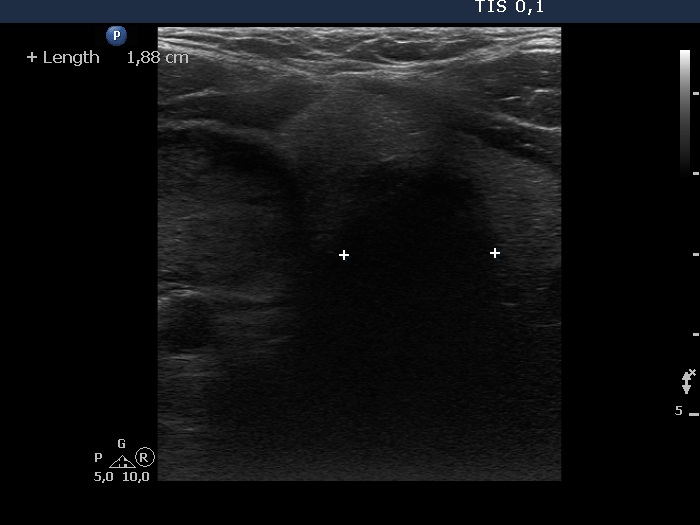

Right lobe, longitudinal scan

Middle part of the neck at the level of the lower part of the thyroid. The diameter of the trachea is narrowed to 19 mm.